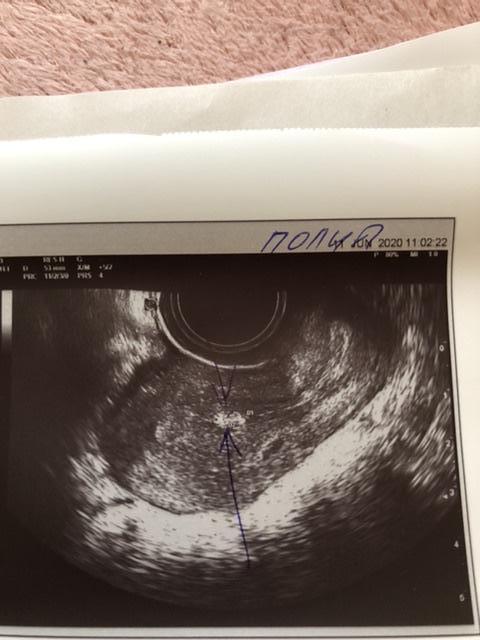

Идёт 4 цикл планирования , решила сходить на узи, на 1 сказали подозрение на полип и киста правого яичника, сегодня была на 2 узи. Кисты в Правом яичнике нет ! Правый яичник с фолликулами до 11 мм, а вот левый содержит доминантный фолликул 20 мм, как думаете когда будет овуляция ? Но , опять увидели это включение размером 7 на 4 мм, сказали с полипом не забеременеешь ! Вопрос кто делал гистероскопию ? Как она прошла ? Или может кто-то забеременел с полипом ? И все же как думаете когда совуляционирует левый яичник ? Эндометрий 10 мм это хороший показатель ?

Я ходила на 9 день размер 8 на 4 мм на 15 день 7 на 4 мм, иду к гинекологу и надеюсь чтоб все обошлось !

Спасибо ! Делала на 9 дц размер 8 на 4 мм, делала на 15 день цикла 7 на 4 мм, уменьшился ? Не понятно , если не полип то что это может быть ?